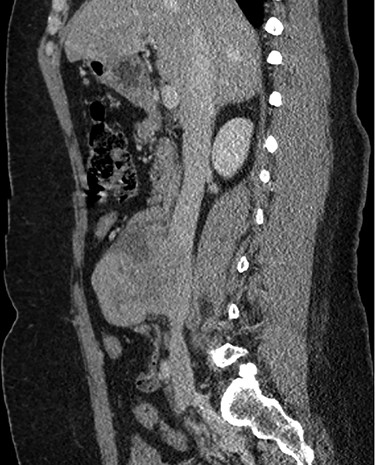

Abdominal CT demonstrating the location of the tumor in the IVC.

The patient had a body mass index of 40, so combined with her presentation, age and gender. The presumptive diagnosis was of gallbladder pathology, which prompted an abdominal ultrasound. Ultrasound revealed a large 7.7 × 6.3 × 7.2 cm heterogenous, hypoechoic masslike lesion overlying the IVC (Fig 1). Abdominal CT was performed, which revealed an 8.9 × 7.9 × 9 cm multilobulated, heterogeneous soft tissue mass in the right hemiabdomen, encasing the IVC and partially encasing the distal abdominal aorta (Figs. 2–4). CT-guided biopsy was performed, which revealed an LMS.

A midline exploratory laparotomy was performed. The tumor extended from inferior to the renal veins to superiorly of the bifurcation. The tumor abutted and partially encased the aorta but did not invade it. Once the tumor was fully mobilized, the patient was heparinized and the vena cava was proximally and distally clamped (Fig 5). The vena cava and tumor were removed en bloc and sent to histopathology. A 22 mm Gelweave Dacron graft was inserted using 5–0 Prolene both proximally and distally (Fig 6). Clamps were removed, and hemostasis was achieved with an overall estimated blood loss of 50 ml. Histopathology of the specimen confirmed an LMS with clear surgical margins.